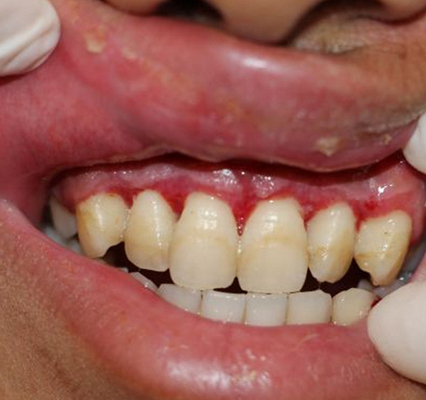

牙齦炎

牙齦炎圖片

牙齦炎和牙周炎